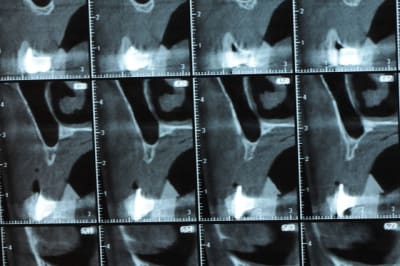

Une petite étude de ton cas D57

Sous réserves bien sur de voir l’animal en vrai

Les zones exploitables radiologiquement parlant:

Coupes implant

2,3 40100

4,96 35130 avec sinus lift mais difficile

5,25 35150

6,02 35130

6,78 35115 après réduction de hauteur de crête

7,26 35115 après réduction de hauteur de crête

8,51 35150

10,43 40115 ou 50115

11,10 40115

Ce qui nous fait 9 implants possible évidement avec un comblement de sinus on augmenterait encore les zones implantable mais ce n’est pas le but recherché, avec 8 (4+4) il doit être possible de faire une belle barre support de complet